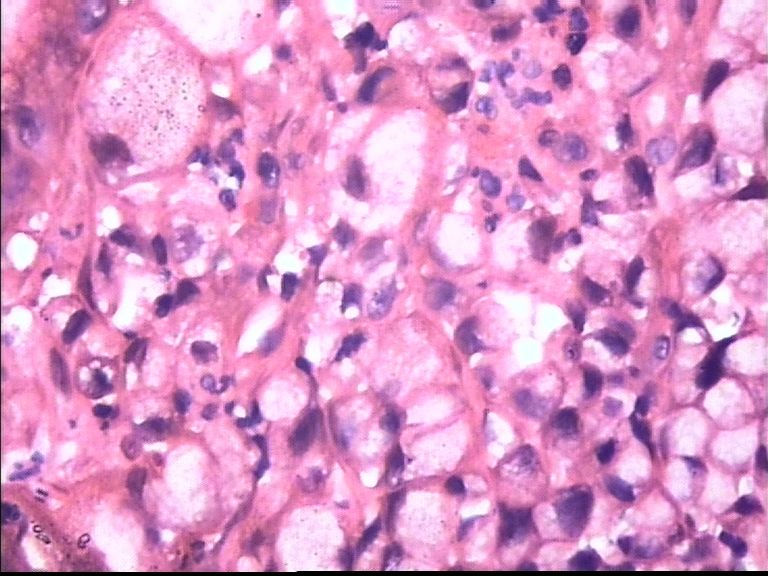

胃部溃疡3cm 53岁 男

• 胃部溃疡3cm 53岁 男图1

图1

仅此局部形态,应该是印戒细胞癌,最好有更多的背景资料

印戒细胞癌

倾向印戒细胞癌

诊断印戒细胞癌

印戒细胞癌高度可疑,建议做:CK、CD68、PAS帮助诊断。